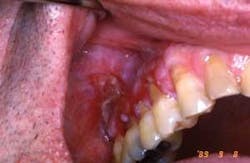

Your patient today is a 34 year-old female who has made an appointment to determine the etiology of an erythematous patch on her right buccal mucosa. She noticed this painless, nonulcerative red area approximately a year ago, but decided to wait until she established a dental office and could make an appointment.

As you evaluate the area, you notice that the erythematous lesion is adjacent to an amalgam restoration. The patient had the restoration placed about 14 months ago — before a job relocation.

After assessing the restoration and later replacing the amalgam with a non-metal restoration, the lesion subsided. It was determined that the cause was due to a sensitivity to the metal components in the restoration or a “contact lichenoid reaction” (see Figure 1).

In the case presented, the reddened area is in contact with the amalgam restoration. The tissue reaction may be around adjacent tissue or possibly at the gingival margin if the restoration extends into the gingival tissue.